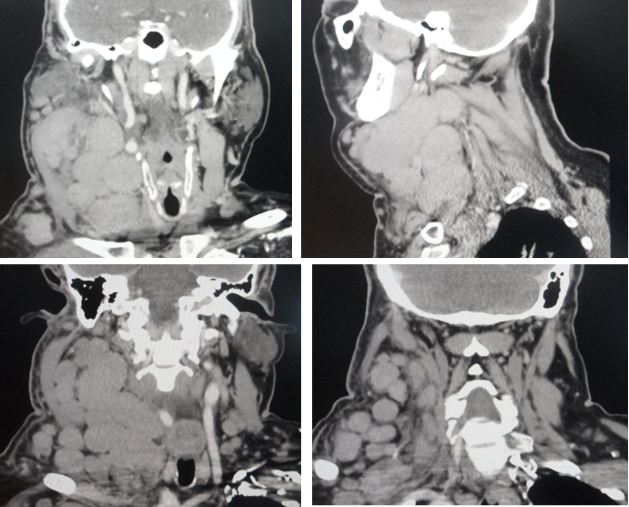

- CT scan showed that there are many lumps all clustered together to cause that swelling.

Medical report of 27 February 2018: Multiple enlarged right level II, bilateral level III and level V and right supraclavicular, right axillary, mediatinum and paraaortic lymphadenopathy. Consistent with recurrence of lymphoma.